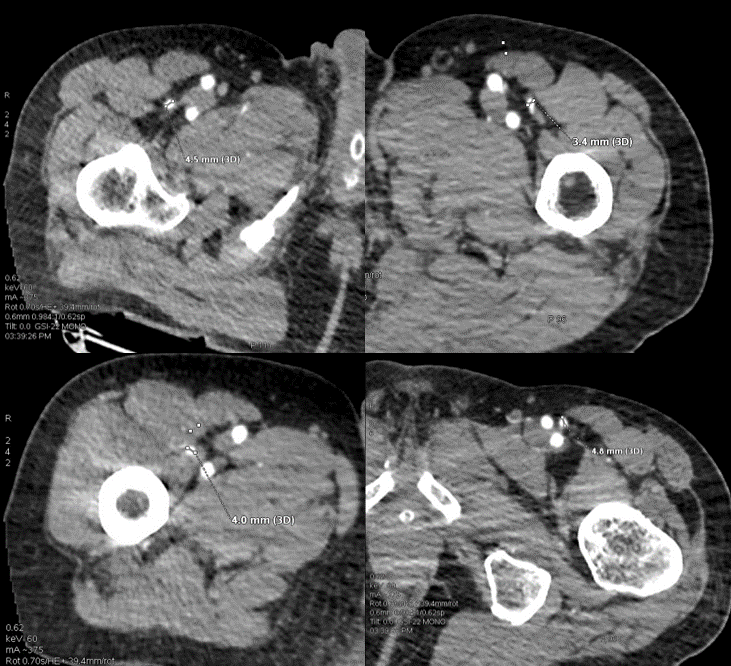

左上肢残端血管状况

60keV单能图像显示残端血流通畅